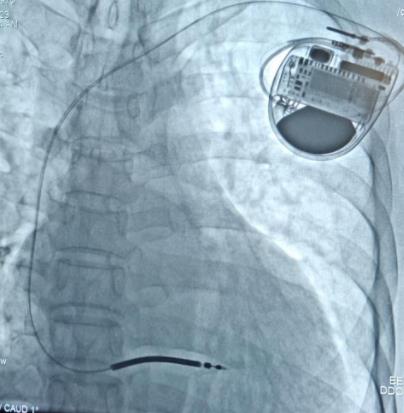

手术过程中,起搏电生理介入治疗团队依靠过硬的技术储备和丰富的操作经验,成功为刘先生进行植入型心律转复除颤器(ICD)手术,术中刘先生各项指标参数良好,血压、心率正常,手术历时1个小时,术后恢复良好,目前已办理出院。

▲术后影像图